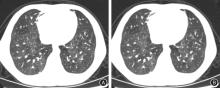

The detection rate of CT signs of DLIR and ASIR-V"

| CT征象 | DLIR-H | ASIR-V80% | χ2值 | P值 |

|---|---|---|---|---|

| 支气管壁增厚 | 146(91.25) | 137(85.63) | 2.475 | 0.116 |

| 空气支气管征 | 111(69.38) | 80(50.00) | 12.481 | < 0.001 |

| 淋巴结肿大 | 53(33.13) | 48(30.00) | 0.362 | 0.548 |

| 间质增厚 | 31(19.38) | 31(19.38) | 0.000 | 1.000 |

| 肺实变影 | 139(86.88) | 115(71.88) | 10.995 | 0.001 |

| 间质浸润 | 33(20.63) | 12(7.50) | 11.404 | 0.001 |

| 胸腔积液 | 40(25.00) | 34(21.25) | 0.633 | 0.426 |